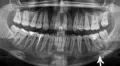

На протяжении всего года болели зубы, сходил к стоматологу, один зуб залечил, а верхний последний зуб, находящийся с правой стороны, не лечил. Сделал снимок, врач сказал, что нужно удалять, я ничего не удалял. После начались ноющие головные боли с правой стороны, иногда отображались на две стороны, одновременно с этим повышалось артериальное давление и притом каждый вечер. Прошёл обследование, оказалось всё нормально.